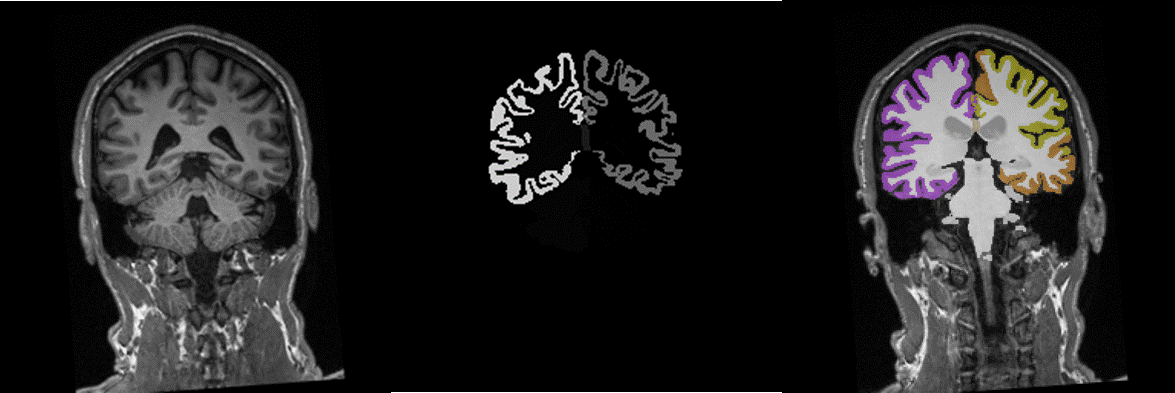

Figure 1. Sample case of original T1-weighted image (left), the corresponding ‘aparc+aseg’  segmentation as generated in FreeSurfer and the nifty-converted segmentation volume overlaid on the original T1-series (using the ‘segment’ colormap in nordicICE)